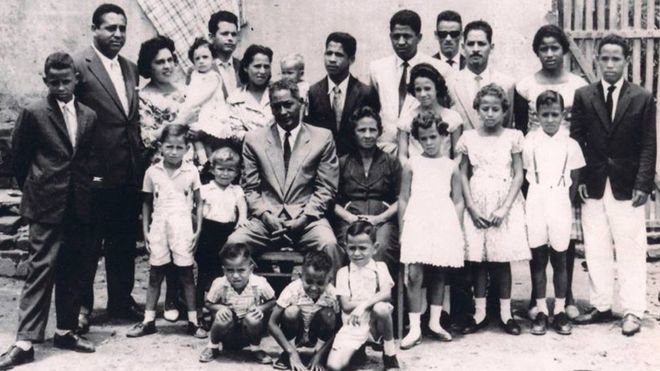

Los abuelos de Vania Nascimento tuvieron 10 hijos, pero perdieron ocho a causa del cáncer. ÁLBUM FAMILIAR

Sus abuelos tuvieron 10 hijos y ocho murieron de cáncer. En la familia más amplia, al menos 20 personas tenían la enfermedad.

Vania fue la primera de la familia en sobrevivir.

“Cada vez que uno de nosotros moría, nos preguntábamos quién sería el siguiente. Nunca entendimos por qué había tantos casos”.